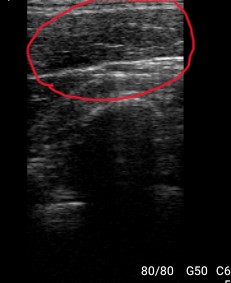

②エコー検査

徒手検査だけでは捉えきれない内部構造を可視化し、正確に状態把握と判断を支援します。

筋肉の動きや炎症所見をリアルタイムに確認することで、施術の精度を高めます。

←施術後:靄が減り、筋肉同士のゆとりが出来て

滑走が良くなった状態